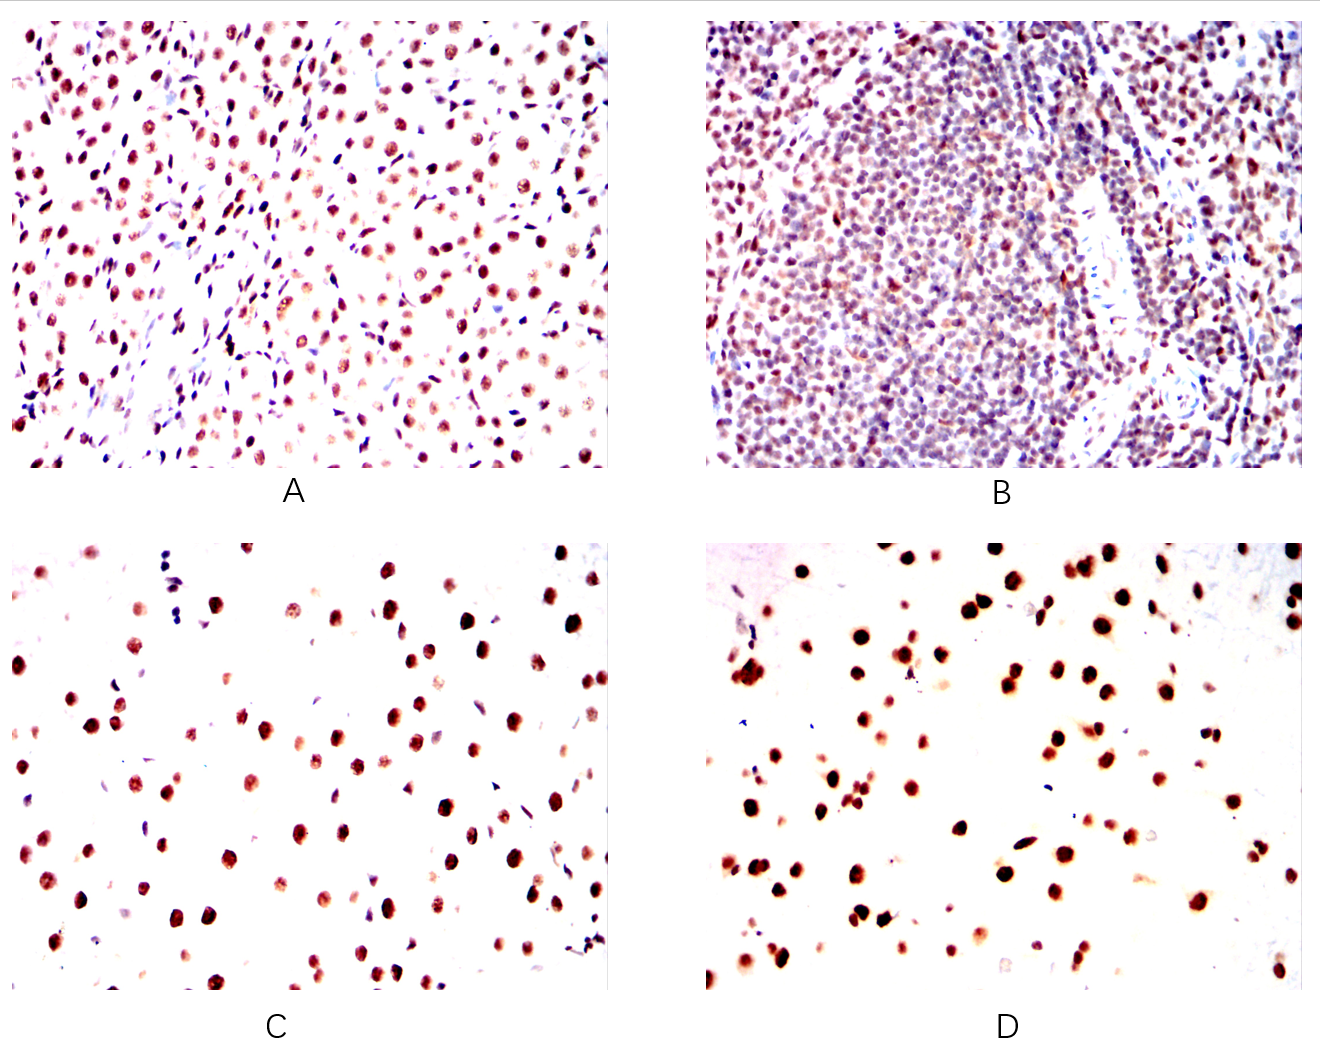

- Immunohistochemical analysis of paraffin-embedded Mouse kidney(A)Mouse spleen(B)Mouse liver(C)Mouse brain(D) using TWIST1 mouse mAb with DAB staining.

- Immunohistochemical analysis of paraffin-embedded Rat kidney(A)Rat spleen(B)Rat liver(C)Rat brain(D) using TWIST1 mouse mAb with DAB staining.

- Immunohistochemical analysis of paraffin-embedded Rabbit kidney(A)Rabbit spleen(B)Rabbit liver(C)Rabbit brain(D) using TWIST1 mouse mAb with DAB staining.